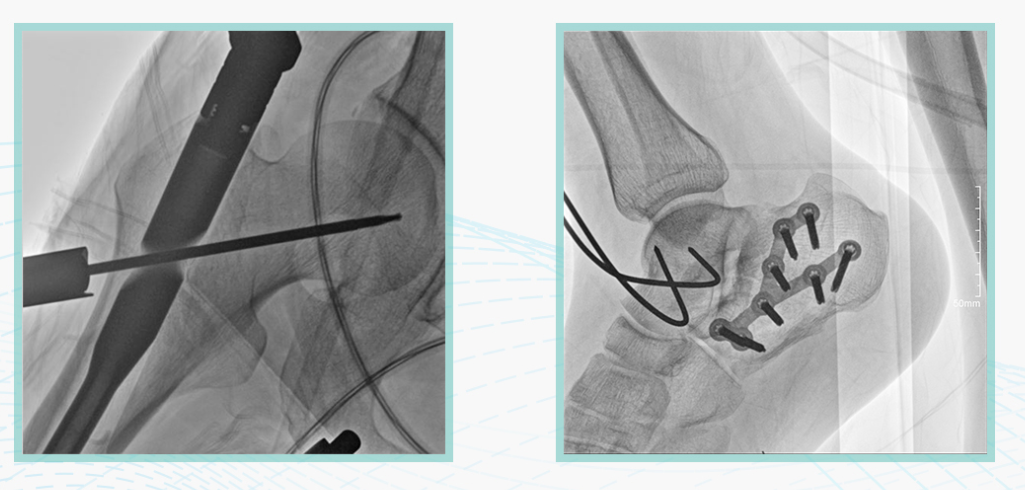

作為全球X線機的主要參與者,安健科技在數字化X線產品線實現全線動態化之外,在移動C臂X光機產品線領域推出全新平板移動C臂產品:悅畫。隨著國家“千縣工程”提升基層醫療衛生服務能力,外科對于手術介入引導設備的需求劇增。對于一臺優秀的移動C臂X線機而言,如何保證最優質影像的同時,最大程度降低X線的輻射劑量,并在滿足臨床手術引導/定位的同時,最大程度的保護臨床手術的醫務人員,是悅畫最為關切的問題。

安健科技悅畫移動C臂X線攝影系統,采用了業內技術最尖端的CMOS探測器。基于性能優異的針狀CSI閃爍體涂層和高靈敏度的CMOS感光芯片,悅畫可以實現在超低X線劑量條件下實現高清晰影像成像,相較于一般的影增移動C臂和平板C臂,動態范圍更高,影像的層次感和對比度更好。

在產品的性能參數設計上,悅畫的像素可達到200萬,空間分辨率可達到3.2線對,采用16bit的影像灰度,悅畫在影像后處理上,通過SPI金字塔圖像算法,支持攝影、脈沖透視影像、連續透視等多種模式下的影像采集,動態透視影像視頻支持保存與回放。雙大屏的設計,透視影像支持三檔放大,保證臨床影像讀取的便利。

此外,骨科手術時間平均時長約為45分鐘左右時間,長期的X線透視或攝影曝光劑量將對臨床手術與操作醫務工作者造成難以評估的健康風險,悅畫通過支持攝影曝光參數的自主調節,可以保證在最低劑量水平下輸出滿足臨床手術定位與引導所需要的影像質量,相較于市面上的固定曝光參數配置移動C臂,自主參數調節設計的曝光功能設計,可以大幅減少醫務工作者的X線輻射劑量。

悅畫在影像的偽影處理上,也積累多項圖像處理專利技術。通過對植入物的精準識別,悅畫能夠精準祛除植入物偽影與運動偽影,保證高質量的影像輸出,無論是影像的對比度、分辨率(清晰度)相較于市面上的移動C臂產品都更勝一籌。